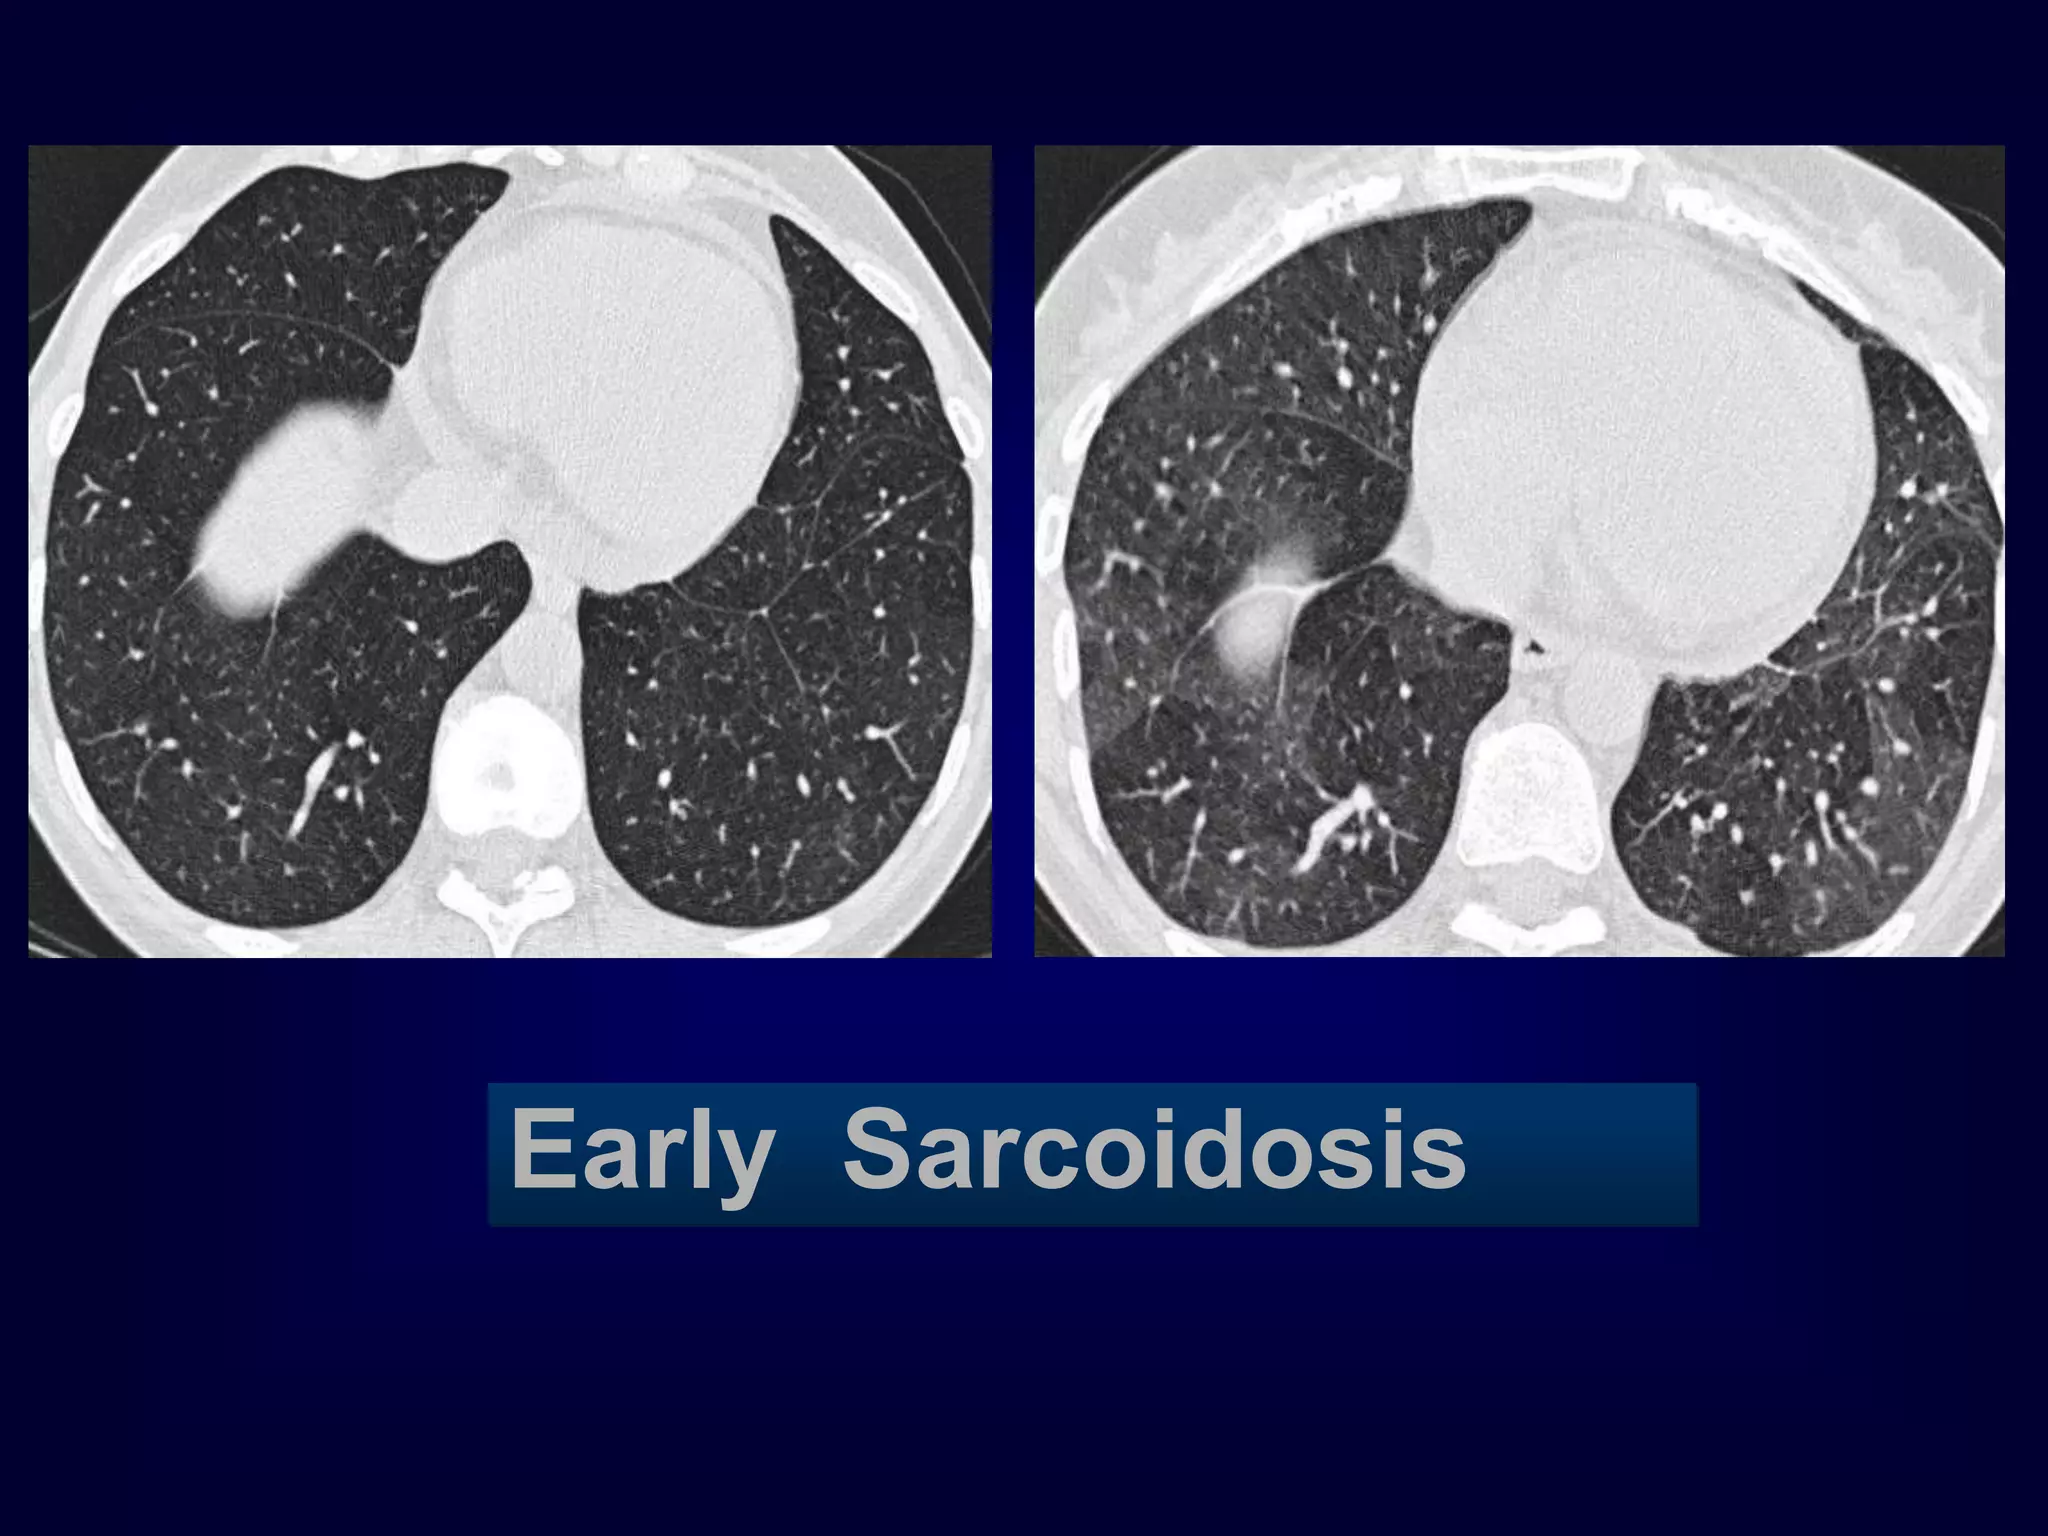

Early Sarcoidosis

Chronic

EAA